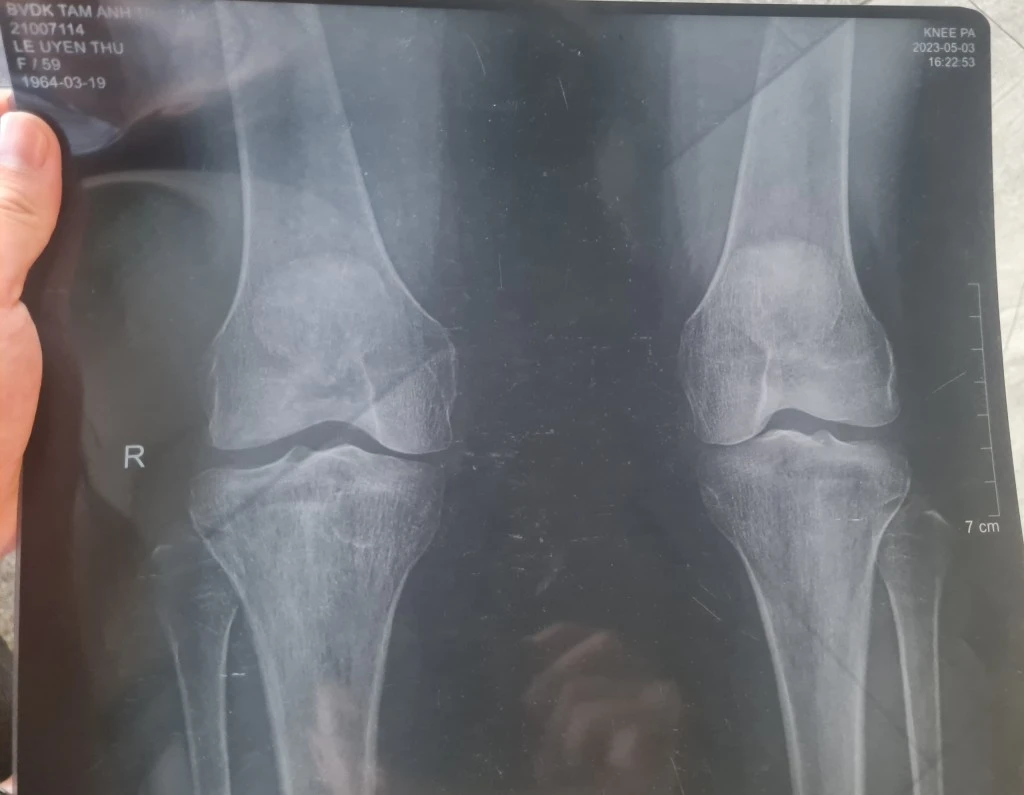

Ngày 3/5/2023, bà tới Bệnh viện Tâm Anh (số 2B Phổ Quang, Phường 2, quận Tân Bình) để khám kiểm tra. Tại đây, bà được bác sĩ Nguyễn Đình Khoa tiến hành khám lâm sàng và chẩn đoán bị viêm dây chằng, bong gân. Sau đó, bà được chỉ định chụp X-quang cả hai đầu gối, đồng thời hẹn một ngày sau đến nhận kết quả.

Theo lịch hẹn, ngày 4/5/2023, bà Uyên Thư trở lại Bệnh viện Tâm Anh và được bác sĩ Đào Duy An Duy đọc kết quả X-quang, kết luận: Thoái hóa khớp gối cả hai bên (trái - phải).

Cụ thể, ở khớp gối phải, 1/3 dưới xương đùi có tình trạng xơ xương dưới sụn và gai xương đầu dưới xương đùi; 1/3 trên hai xương cẳng chân có tình trạng xơ xương dưới sụn và gai xương đầu trên xương chày; phần xương bánh chè bị xơ xương dưới sụn và gai xương.

Tương tự, ở khớp gối trái: 1/3 dưới xương đùi có tình trạng bị gai xương và xơ xương dưới sụn đầu dưới xương đùi; 1/3 trên hai xương cẳng chân bị gai xương và xơ xương dưới sụn đầu trên xương chày; xương bánh chè bị gai xương rìa.

Với tình trạng bệnh nêu trên, bác sĩ Đào Duy An Duy khuyên bà Uyên Thư nên tiêm HA mỗi gối giá 6 triệu đồng. Tuy nhiên, bà Uyên Thư thấy chân trái của mình hoàn toàn khỏe mạnh, chân phải cũng chỉ hơi nhức nên quyết định chưa tiêm.

Bà Uyên Thư nghi ngờ kết quả chụp X-quang và chẩn đoán bệnh của bác sĩ Bệnh viện Tâm Anh không đúng nên đã đến một số cơ sở y tế khác để chụp lại X-quang và MRI. Tuy nhiên, kết quả chẩn đoán mỗi nơi vào từng thời điểm lại không giống nhau.

Tại Bệnh viện Đại học Y dược TP HCM, kết quả chụp cộng hưởng từ (MRI) khớp gối ngày 4/8/2023 có kết luận: Bà Thư bị thoái hóa khớp gối trái - phải. Trong khi đó, hơn 2 tháng sau, kết quả chụp X-quang tại Trung tâm Y khoa Medic (thuộc Công ty TNHH Y tế Hòa Hảo) ngày 20/10/2023: Không phát hiện bệnh lý trên phim X-Quang cả hai khớp gối trái - phải.

Khách hàng khởi kiện Bệnh viện Tâm Anh vì lý do Bà Thư nghi ngờ kết quả chụp X-quang và chẩn đoán bệnh của bác sĩ Bệnh viện Tâm Anh không đúng với tình trạng bệnh (Ảnh chụp X-quang khớp gối của bà Thư)

Từ những nhận định nêu trên, bà Thư "nghi ngờ Bệnh viện Tâm Anh lấy kết quả chụp X-quang của một bệnh nhân khác đưa cho bà với mục đích dụ dỗ bà tiêm HA với giá 12 triệu/2 gối". Bà cũng cho rằng, vì chẩn đoán sai bệnh ngay từ đầu nên dẫn tới việc phải chạy chữa nhiều nơi, tốn nhiều tiền bạc, công sức và ảnh hưởng đến sức khỏe, tinh thần.

Hội đồng chuyên môn kết luận: Không có sự nhầm lẫn trong việc chụp X-quang hai khớp gối của bà Uyên Thư vào ngày 3 - 4/5/2023. Hội đồng cũng cho rằng, triệu chứng lâm sàng và kết quả X-quang khớp gối thời điểm bà Thư thăm khám là phù hợp với chẩn đoán.